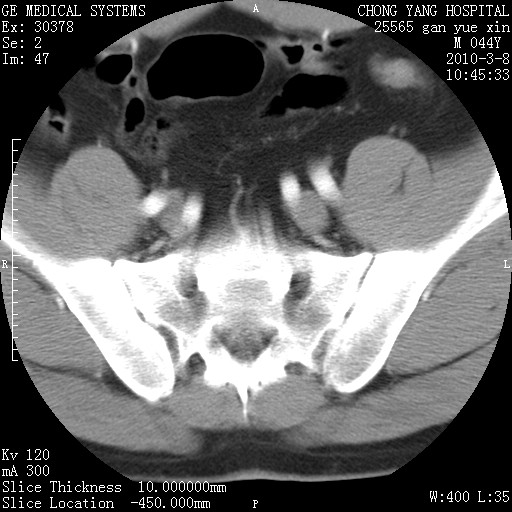

标题: CT24940:主动脉增强,典型病例。 [打印本页]

标题: CT24940:主动脉增强,典型病例。

夹层动脉瘤。

动脉夹层

夹层动脉瘤,典型

主动脉夹层。

动脉夹层的分型:

⒈debakey分型:根据主动脉夹层累及部位,分为三型:ⅰ型:原发破口位于升主动脉或主动脉弓部,夹层累及升主动脉、主动脉弓部、胸主动脉、腹主动脉大部或全部,少数可累及髂动脉。ⅱ型:原发破口位于升主动脉,夹层累及升主动脉,少数可累及部分主动脉弓。ⅲ型:原发破口位于左锁骨下动脉开口远端,根据夹层累及范围又分为ⅲa,ⅲb。ⅲa型:夹层累及胸主动脉。ⅲb型:夹层累及升主动脉、腹主动脉大部或全部。少数可累及髂动脉。

⒉stanford分型:a型:夹层累及升主动脉,无论远端范围如何。b型:夹层累及左锁骨下动脉开口以远的降主动脉。

夹层动脉瘤,少量胸水

夹层动脉瘤;左侧少量胸腔积液。

典型主动脉夹层。